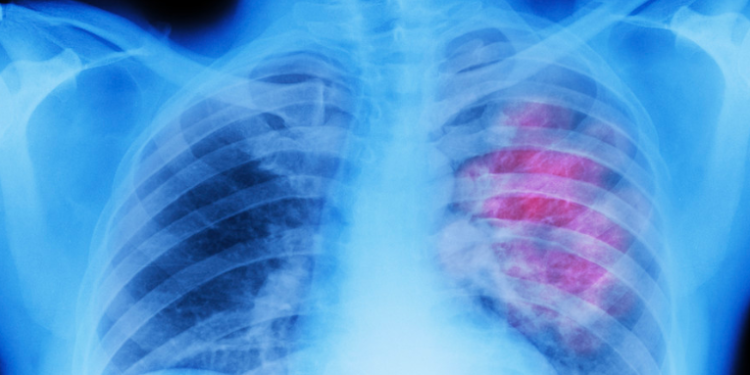

Los principales cánceres en términos de muertes que podrían haberse prevenido fueron los de tráquea, bronquios y pulmón tanto para hombres como para mujeres.